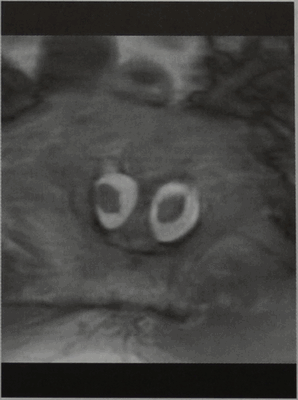

МРТ, Т1-взвешенное изображение (горизонтальная проекция, GE). Визуализируются две половины спинного мозга. Справа определяются спайки с костной перегородкой.